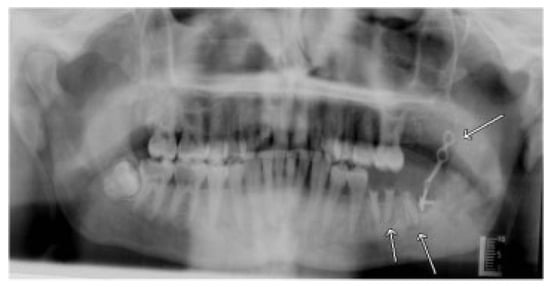

A Prospective Study of Strut Versus Miniplate for Fractures of Mandibular Angle